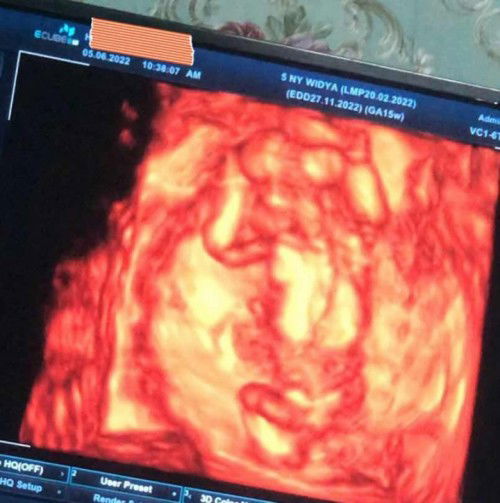

Bund mau tanya apa iya usia kandungan 13/14w itu djj nya kadang masih samar soalnya pas saya cek di bidan pake doppler masih samar tapi waktu saya usg dihalobumil cibubur cek usia kandungan 9w sudah ada janin dan djj nya terdengar jelas semalam saya cek kebidan katanya masih samar#ingintahu ( padahal ini kehamilan ke2 saya)🤦🏻♀️